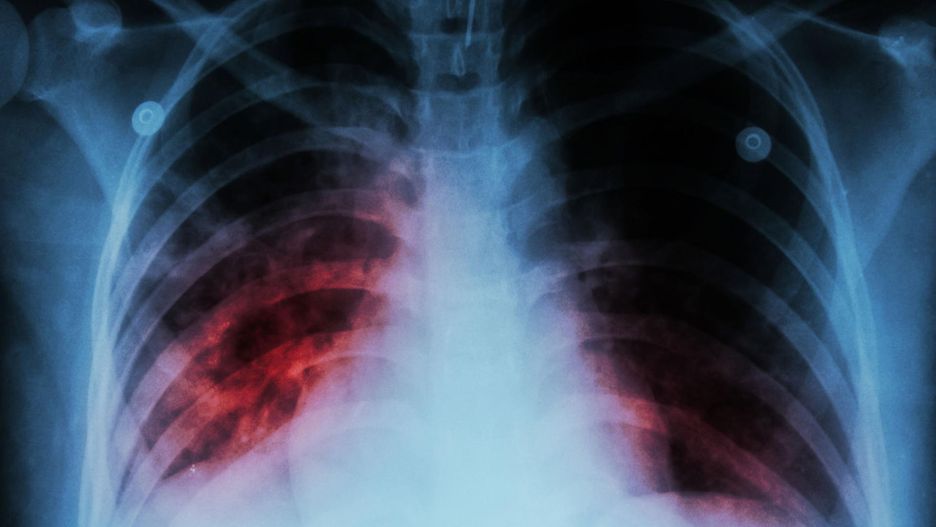

POChP od wielu lat znajduje się w czołówce chorób niebezpiecznych. Co godzinę w Polsce z powodu tej nieuleczalnej choroby umierają dwie osoby. Zajmuje czwarte miejsce wśród najczęstszych przyczyn zgonów. Mimo tych niepokojących statystyk, świadomość Polaków na temat choroby niska.

Mimo, że POChP jest chorobą niebezpieczną, z medycznego punktu nie tak trudno ją wykryć. Badanie spirometryczne jest podstawową formą diagnozy przewlekłej obturacyjnej choroby płuc. Spirometria jest bezbolesna, nie wymaga przygotowań, trwa kilka minut, a daje cenne informacje: pozwala ocenić pracę i pojemność płuc. Powinien ją zrobić każdy palacz papierosów, ponieważ głównym czynnikiem wpływającym na POChP jest dym papierosowy, który odpowiada za 90 proc. zachorowań. Pozostałe 10 proc. chorych to ci, których płuca narażone są na wdychanie toksyn, np. lakiernicy, stolarze, malarze. Niestety, według raportu przeprowadzonego w ramach kampanii Płuca Polski tylko 0,5 proc. Polaków pytanych o to, co kojarzy im się z POChP, wymieniało spirometrię.

- Przewlekła obturacyjna choroba płuc dotyka głównie osoby w średnim i starszym wieku. Z powodu niskiej świadomości, pacjenci często zgłaszają się do lekarza w zaawansowanym stadium choroby. 75 proc. chorych Polaków żyje w nieświadomości, lekceważąc pierwsze objawy choroby. Dlatego my - pulmonolodzy tak często podkreślamy, że niezwykle ważne jest, aby lekarze pierwszego kontaktu zachęcali pacjentów do wykonywania kontrolnych badań spirometrycznych. Wczesna diagnoza POChP może poprawić jakość życia pacjenta. Profilaktyczne wykonywanie badań zmniejszy ryzyko niezauważenia niespecyficznych objawów choroby, które często są mylone ze słabą kondycją organizmu – komentuje prof. dr hab. n. med. Adam Antczak, ekspert kampanii Płuca Polski.

Niepokojącymi objawami są: duszność trwająca kilka miesięcy, świszczący oddech, ucisk w klatce piersiowej oraz uporczywy kaszel z odkrztuszaniem wydzieliny.